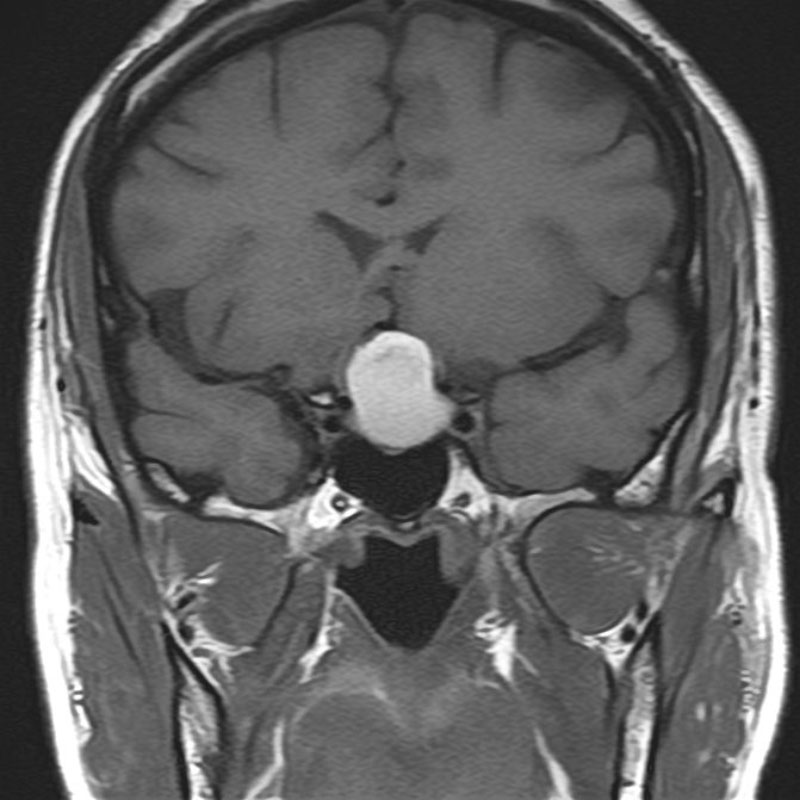

No.’25_107 手術前1

No.’25_107 手術前2